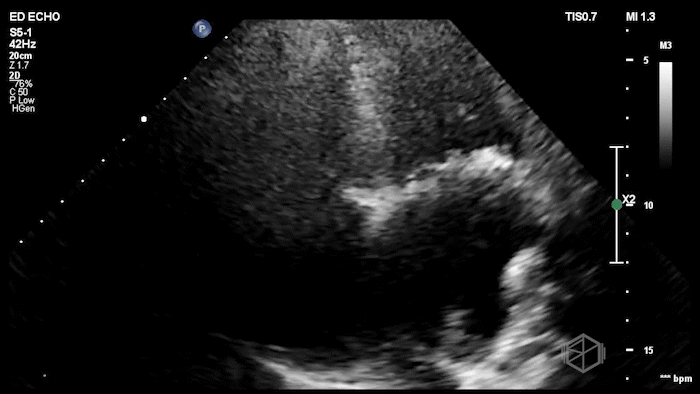

Here is the POCUS:

The POCUS shows a probably borderline LV systolic function. There is significant mitral valve calcification present. There is a mobile echodensity present near the mitral valve. On the color doppler there is severe mitral regurgitation.

In the ED, markedly elevated troponin (~42,000) and BNP 1520. Cardiology TTE revealed a 1.4 × 0.7 cm mobile echodensity on the mitral valve, concerning for papillary muscle or chordal rupture, with differential also including flail leaflet vs. vegetation, in the setting of wall motion abnormalities. The patient had a cath that showed severe triple-vessel CAD, prompting IABP placement and ICU admission. TEE confirmed severe MR due to chordal rupture with preserved LV function. She eventually did get a mitral valve replacement, but had a complex course and ultimately was made comfort care.